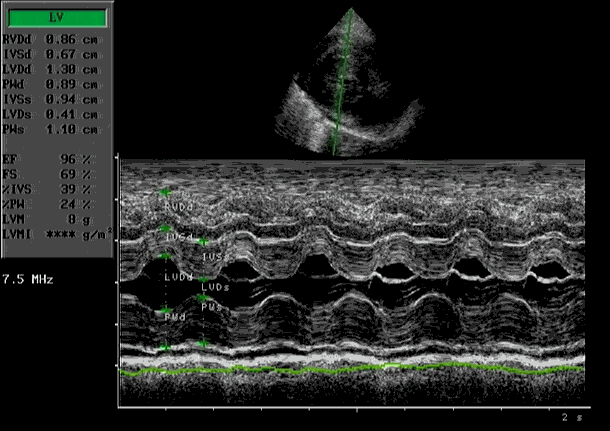

De diagnose kan alleen gesteld worden met een echocardiogram gecombineerd met kleuren Doppler.

Dit onderzoek zegt niet alleen iets over de beweging en grootte van de diverse hart-structuren, maar ook iets over het functioneren van het hart. De wanden van het normale hart zijn normaal 0,55-06 cm. Bij HCM is dit vaak meer dan 0,9 cm.

Verdikte wanden linker kamer | Flowmeting met Doppler |

M-mode met abnormale mitraalklepbeweging | (foto: Putcuyps) |